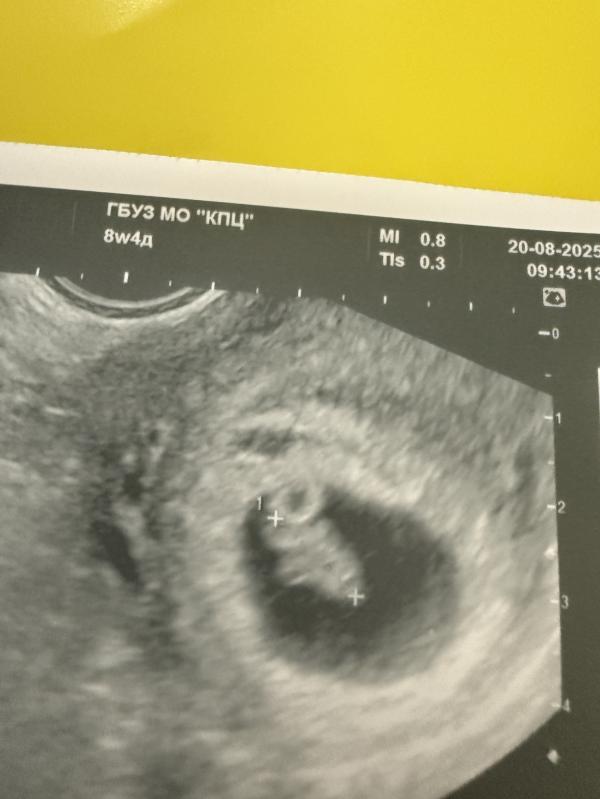

Третье узи на сроке 8.4 недель по месячным

Ктр - 11.6 мм что соответствует 7.2

Получается , что уже отставание еще на 4 дня появилось. Почему рос ровно , а тут замедлился? 😢